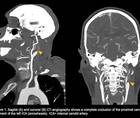

Ischemic Complications from a Facial Lipofilling Procedure

Sanaz Rezaei, MD; Fatemeh Talebi, MDSanaz Rezaei, MD; Fatemeh Talebi, MD - Stroke